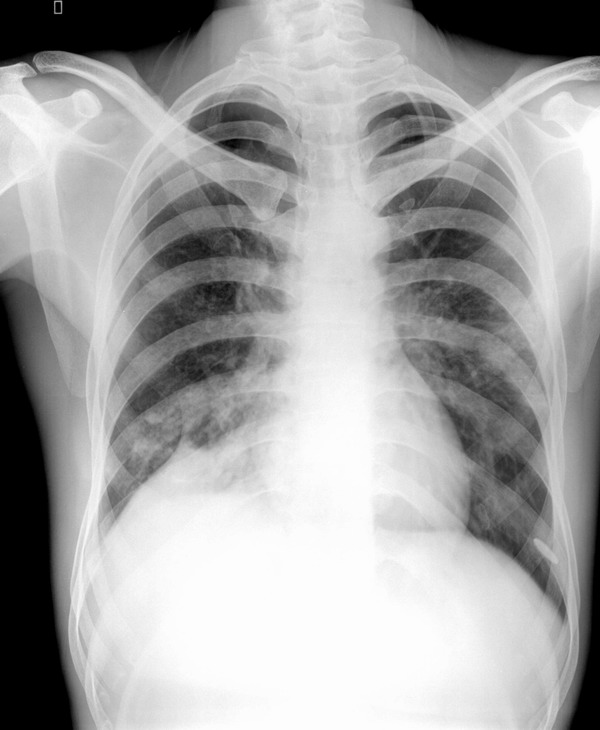

男,34y,发热寒颤月余,脓痰!

右下肺沿支气管的小结结影,还发现粘连性改变,侧位可见后肋隔角消失,因此考虑:支气管肺炎,脓旬,包裹性积液

右下肺沿支气管的小结结影,还发现粘连性改变,侧位可见后肋隔角消失,因此考虑:支气管肺炎,脓胸,包裹性积液

颈肋.右肺下叶后基底段及左肺下叶背段炎变伴右侧胸腔包裹性积液

右下肺炎,右侧胸膜肥厚,右侧胸腔积液,双侧颈肋.

右肺下叶肺脓肿并胸腔积液

右肺下叶肺脓肿并胸腔积液,胸膜粘连.左肺炎症.颈肋.

1 双侧颈肋.  2右下肺炎,3左上叶前段节段性肺炎4右侧叶间积液?

右下肺炎,包裹性积液

右下肺炎症,拌肺底积液